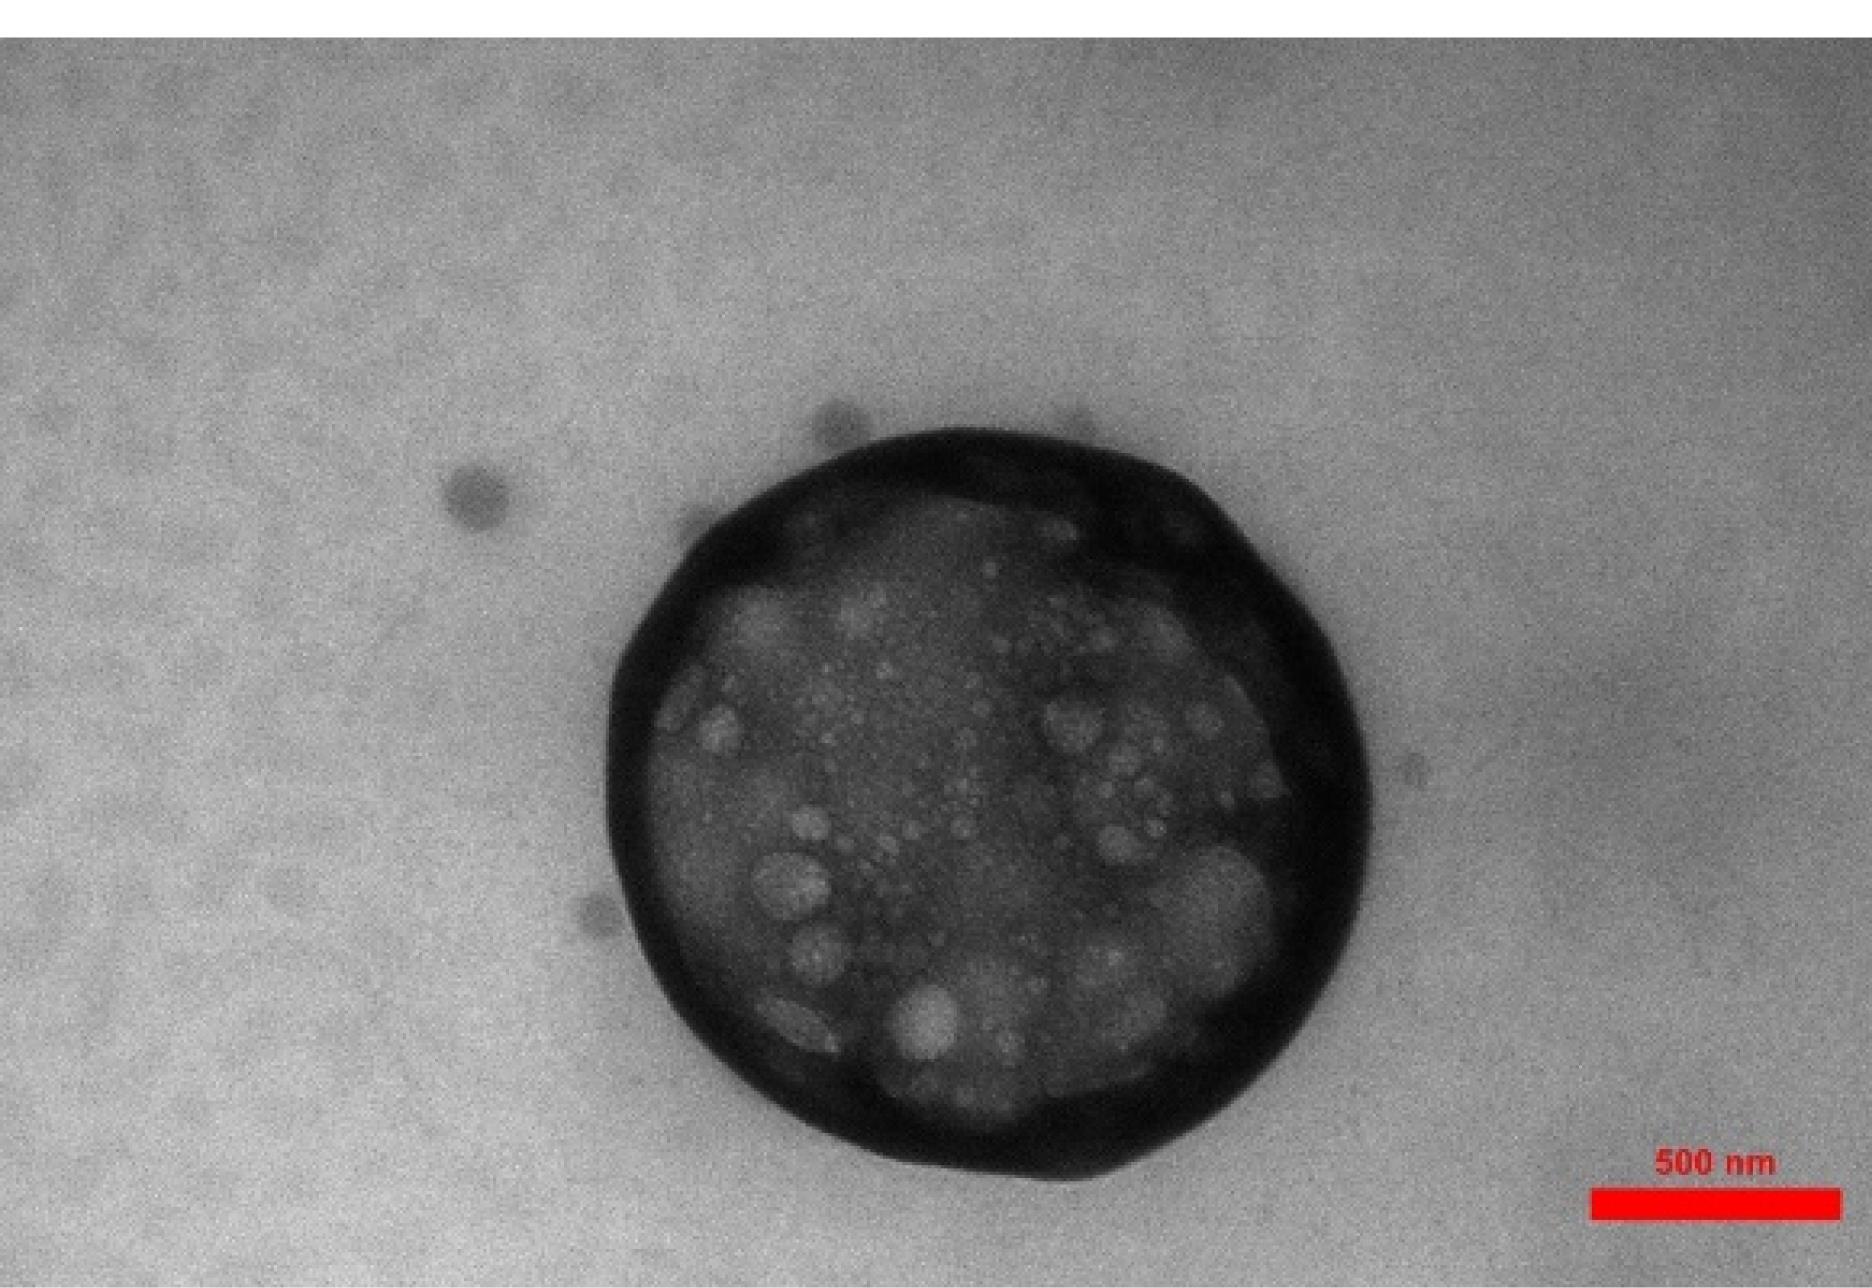

Formulation 6 (F6) was chosen as the optimal preparation to show nanoparticle microscopy images, as shown in Figure 1. Figure 1 depicts spherical chitosan-coated NLC particles, clearly exhibiting the presence of the chitosan coat surrounding the NLCs.

TEM pictures of F6 (chosen preparation)

The difference in size between the DLS and TEM results can be attributed to several factors: Measurement technique, Sample preparation, Instrument limitations, and Sample characteristics. The measurement technique is one of the most important factors that affect size variation. The authors discussed the reason for this difference in size between DLS and TEM results. DLS measures the hydrodynamic size of particles or molecules in a solution, while TEM directly images the size of individual particles using an electron beam. DLS provides an average size based on the Brownian motion of particles, whereas TEM provides direct visualization of individual particles.26